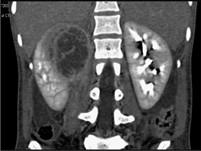

问题 女,32岁,右腰部疼痛伴高热,请根据所示图像,选择最可能诊断 ( )

选项 A、右肾囊肿合并感染 B、右侧急性肾盂肾炎 C、右肾结核 D、右肾脓肿 E、右肾囊性肾癌

答案 D